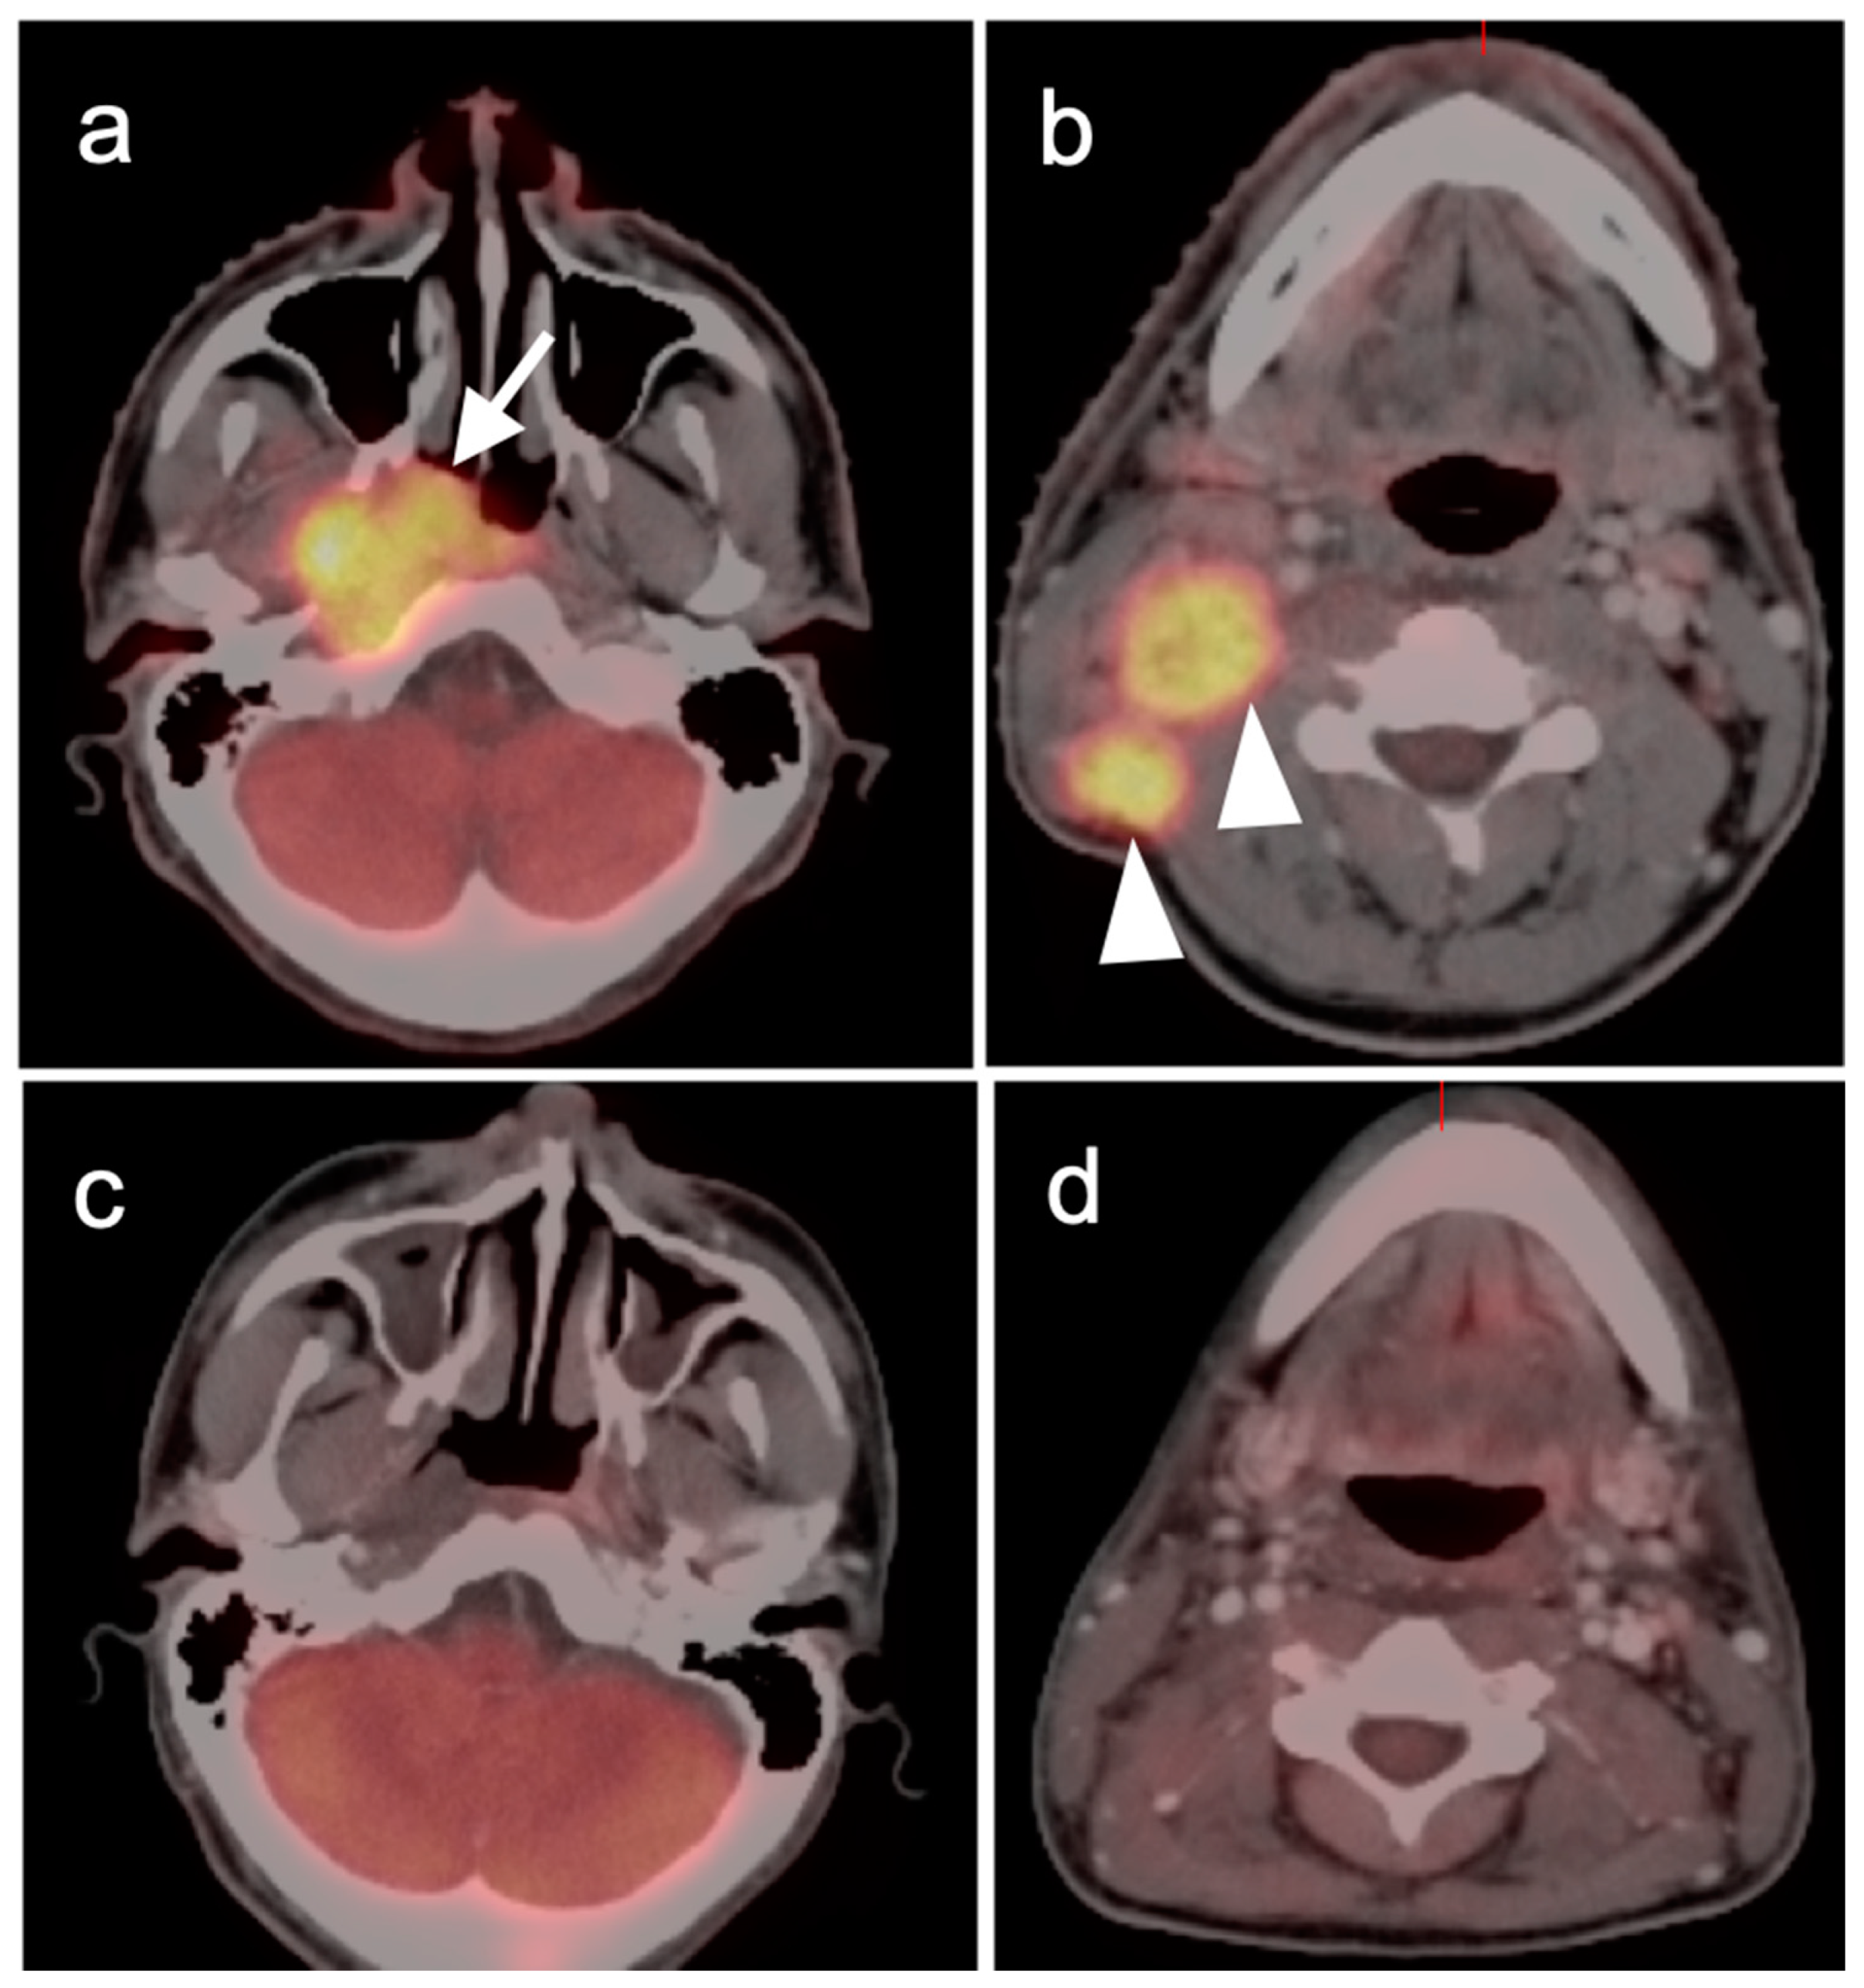

2.3. Nasopharyngeal Carcinoma

2.4. Sinonasal Tumors